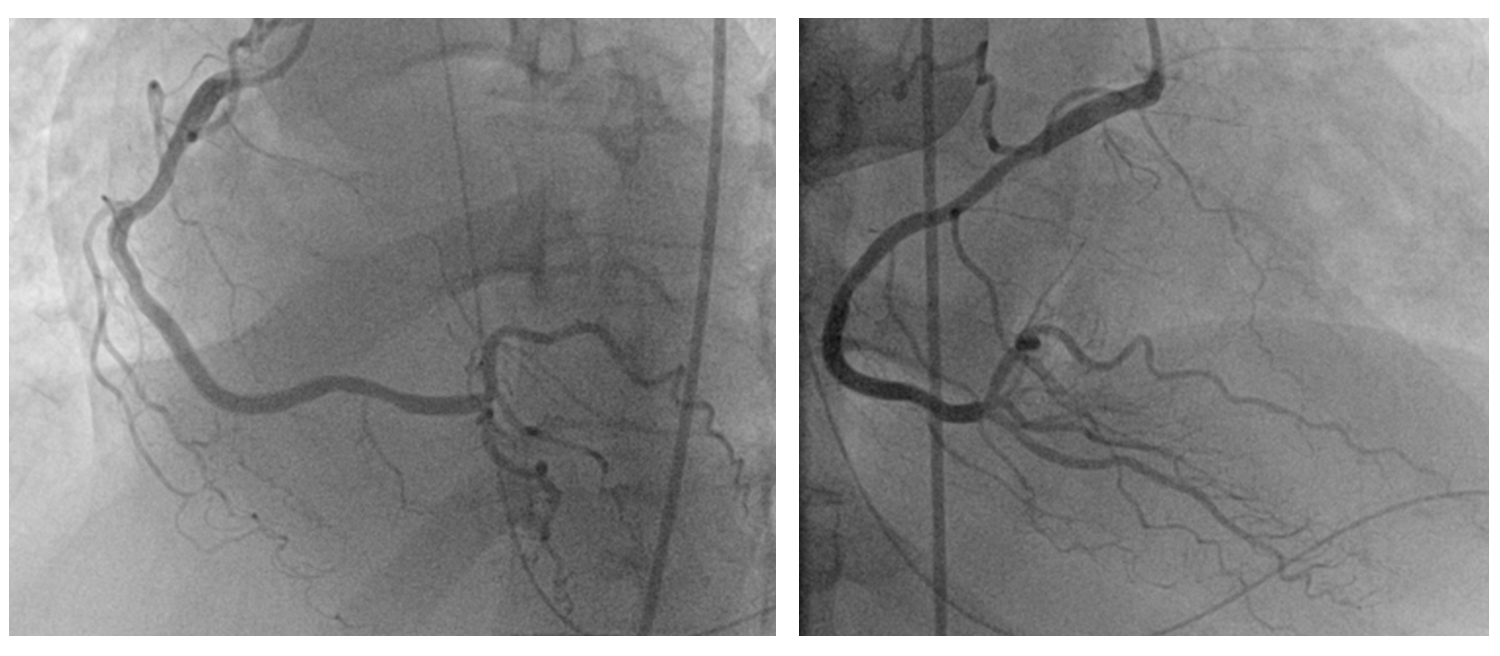

Due to a weak radial pulse, right femoral artery access was obtained for coronary angiography. A 6 French sheath was inserted. Angiography revealed : 95% stenosis with calcification of the distal left main coronary artery (LMCA), 70-80% stenosis of the proximal - mid left anterior descending artery (LAD), 50%-60% stenosis of the proximal left circumflex artery (LCx) and normal right coronary artery (RCA).

Percutaneous coronary intervention (PCI) of the LMCA-LAD lesion was performed with intra-aortic balloon pump (IABP) support. A 6 French EBU 3.5 guiding catheter was used to engage the left coronary artery. After wiring the lesion with a moderate support wire, intravascular ultrasound (IVUS) revealed an eruptive calcified nodule in the distal LMCA and heavy calcification (270-360 degrees) in the LAD. Rotablation was performed with a 1.5 mm burr for 3 runs. Following rotablation, the LAD wire was lost but successfully rewired. The LMCA-LAD lesion was predilated with a 3.0 x 15 mm non-compliant (NC) balloon. Provisional crossover stenting of the LMCA-LAD was performed with a 3.0 x 38 mm drug-eluting stent (DES). Proximal optimization was achieved with a 4.0 x 8 mm NC balloon inflated to 16 atmospheres (ATM) in the LMCA. The proximal-mid LAD was post-dilated with a 3.0 x 15 mm NC balloon inflated to 12 ATM. Repeat IVUS demonstrated good stent apposition and landing zones with no edge dissection, but the minimal stent area (MSA) in the proximal LAD required further optimization. Final post-dilation in proximal LAD with a 3.5 x 12 mm non-compliant (NC) balloon inflated to 16 ATM resulted in a good final angiographic result and IVUS-confirmed MSA of 8.01 mm2 in the LAD and 12.24 mm2 in the LMCA.